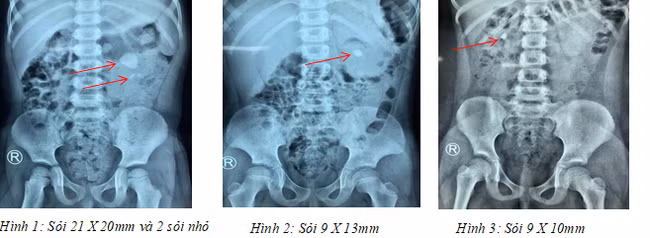

BV Bình Dân TPHCM tiếp nhận từ BV Nhi đồng tại TP.HCM các cháu V.N.K (3 tuổi, TP.HCM) có sỏi kích thước 21x20 mm cùng 2 sỏi nhỏ ở thận trái, P.Đ.N.Y (7 tuổi, TP.HCM) có sỏi 9x10 mm ở thận phải, N.T.T.N (6 tuổi, Cần Thơ) có sỏi 9x13 mm ở thận trái.

Các ca phẫu thuật diễn ra trong hơn 1 giờ với sự phối hợp với các bác sĩ gây mê nhi từ BV Nhi Đồng 1. Hình ảnh kiểm tra sau phẫu thuật cho thấy thận đã sạch sỏi hoàn toàn. Ba bệnh nhi ra viện trong niềm vui khôn xiết của gia đình.